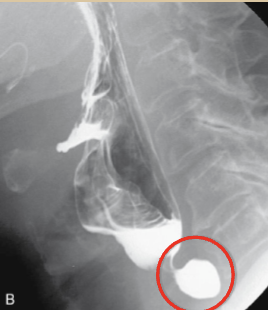

<p>What esophageal disorder is this?</p>

What esophageal disorder is this?

Schatzki’s ring